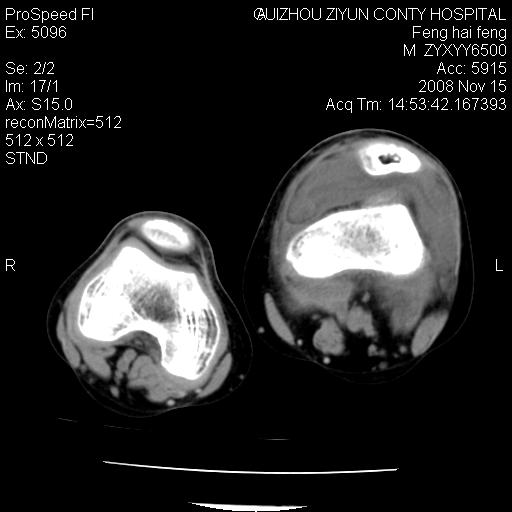

标题: CT16656:M 14Y 左膝关节肿胀一年余。其余病史不详。 [打印本页]

标题: CT16656:M 14Y 左膝关节肿胀一年余。其余病史不详。

考虑左侧髌骨结核;左膝关节滑膜肿胀、增厚,关节囊积液。

左膝滑膜型关节结核可能性大!支持!滑膜型关节结核主要ct表现:关节囊肿胀,积液,关节面见小破坏灶,并见点状死骨!

好大的左腿!考虑左侧髌骨结核,左膝关节滑膜肿胀、增厚,关节囊积液。

左侧髌骨结核;左膝关节滑膜肿胀、增厚,关节囊积液